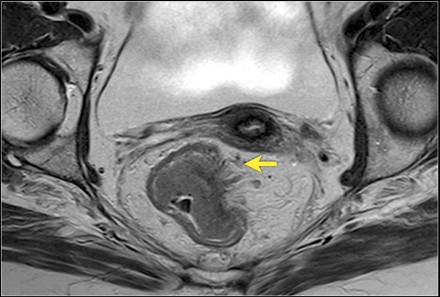

- Đánh giá di căn hạch vùng trên cộng hưởng từ:

Theo AJCC hạch vùng bao gồm: quanh trực tràng, mạc treo sigma, dưới mạc treo, bên cùng, trước cùng, chậu trong, Gerota, chậu ngoài, trực tràng trên, trực tràng giữa, trực tràng dưới.

Một hạch nghi ngờ là hạch di căn trên CHT khi thuộc một trong ba  trường hợp sau:

- Trường hợp thứ nhất, hạch có kích thước <5mm kèm với ba đặc điểm ác tính (hạch bờ không đều, tín hiệu hạch không đồng nhất, hạch hình tròn).

- Trường hợp thứ hai, hạch có kích thước 5-9mm kèm hai trong ba đặc điểm ác tính (hạch bờ không đều, tín hiệu hạch không đồng nhất, hạch hình tròn).

- Trường hợp thứ ba, hạch có kích thước  >9mm luôn luôn xem là hạch nghi ngờ.

Hình 9. Hai hạch nghi ngờ di căn ở phía trong cân mạc treo trực tràng